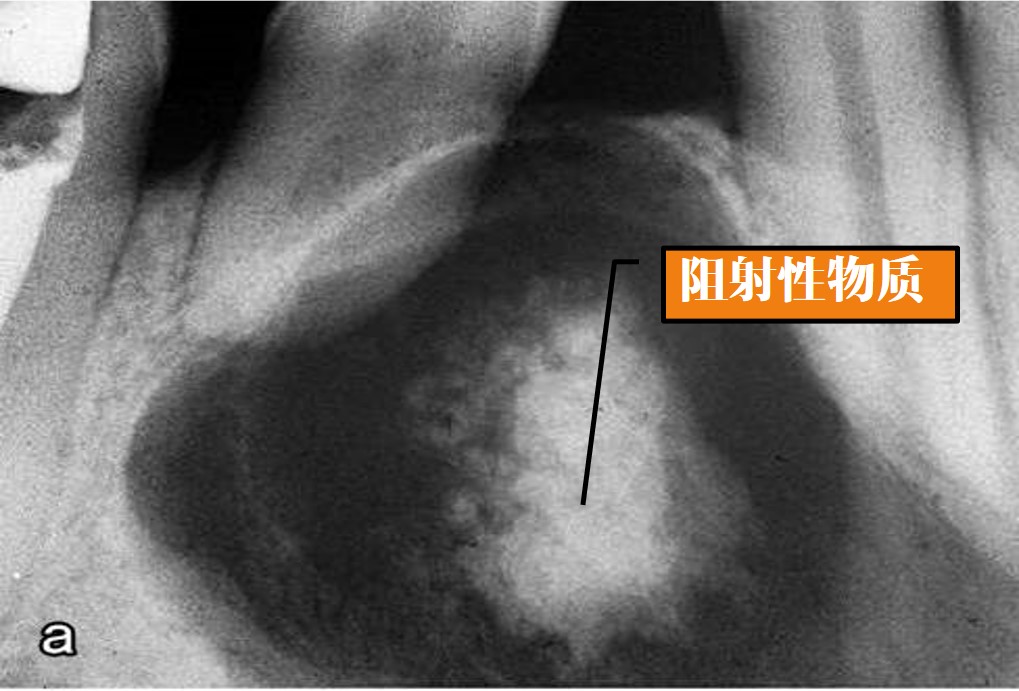

任何年龄,平均年龄30岁,好发部位为颌骨前份,有时也可发生于颌骨外的软组织,X线表现为界限清楚的放射透光区,单房或多房(图13.1-10),有时可伴有牙瘤发生。

图13.1-10 牙源性钙化囊肿(X线)

2)病理变化:

光镜下:病变呈囊性,衬里上皮的基底细胞呈立方状或柱状,胞核远离基底膜,其浅层由排列疏松的星形细胞构成,类似于星网状层,衬里上皮和纤维囊壁内可见数量不等的影细胞灶,并有不同程度的钙化(图13.1-11)。影细胞呈圆形或卵圆形,境界清楚,胞质红染,胞核消失而不着色,在胞核部位形成阴影(图13.1-12)。